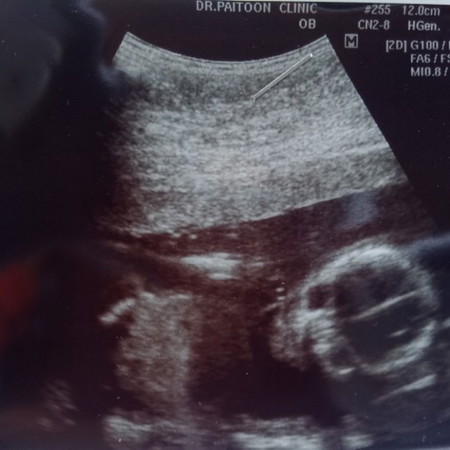

18w2d

หมอบอก ชาย 99%

ใบซาวนี้เป็นใบหน้าคะแม่ ยินดีด้วยนะคะ

18w2d หมอบอกผู้ชาย 100% เลยค่ะแม่55